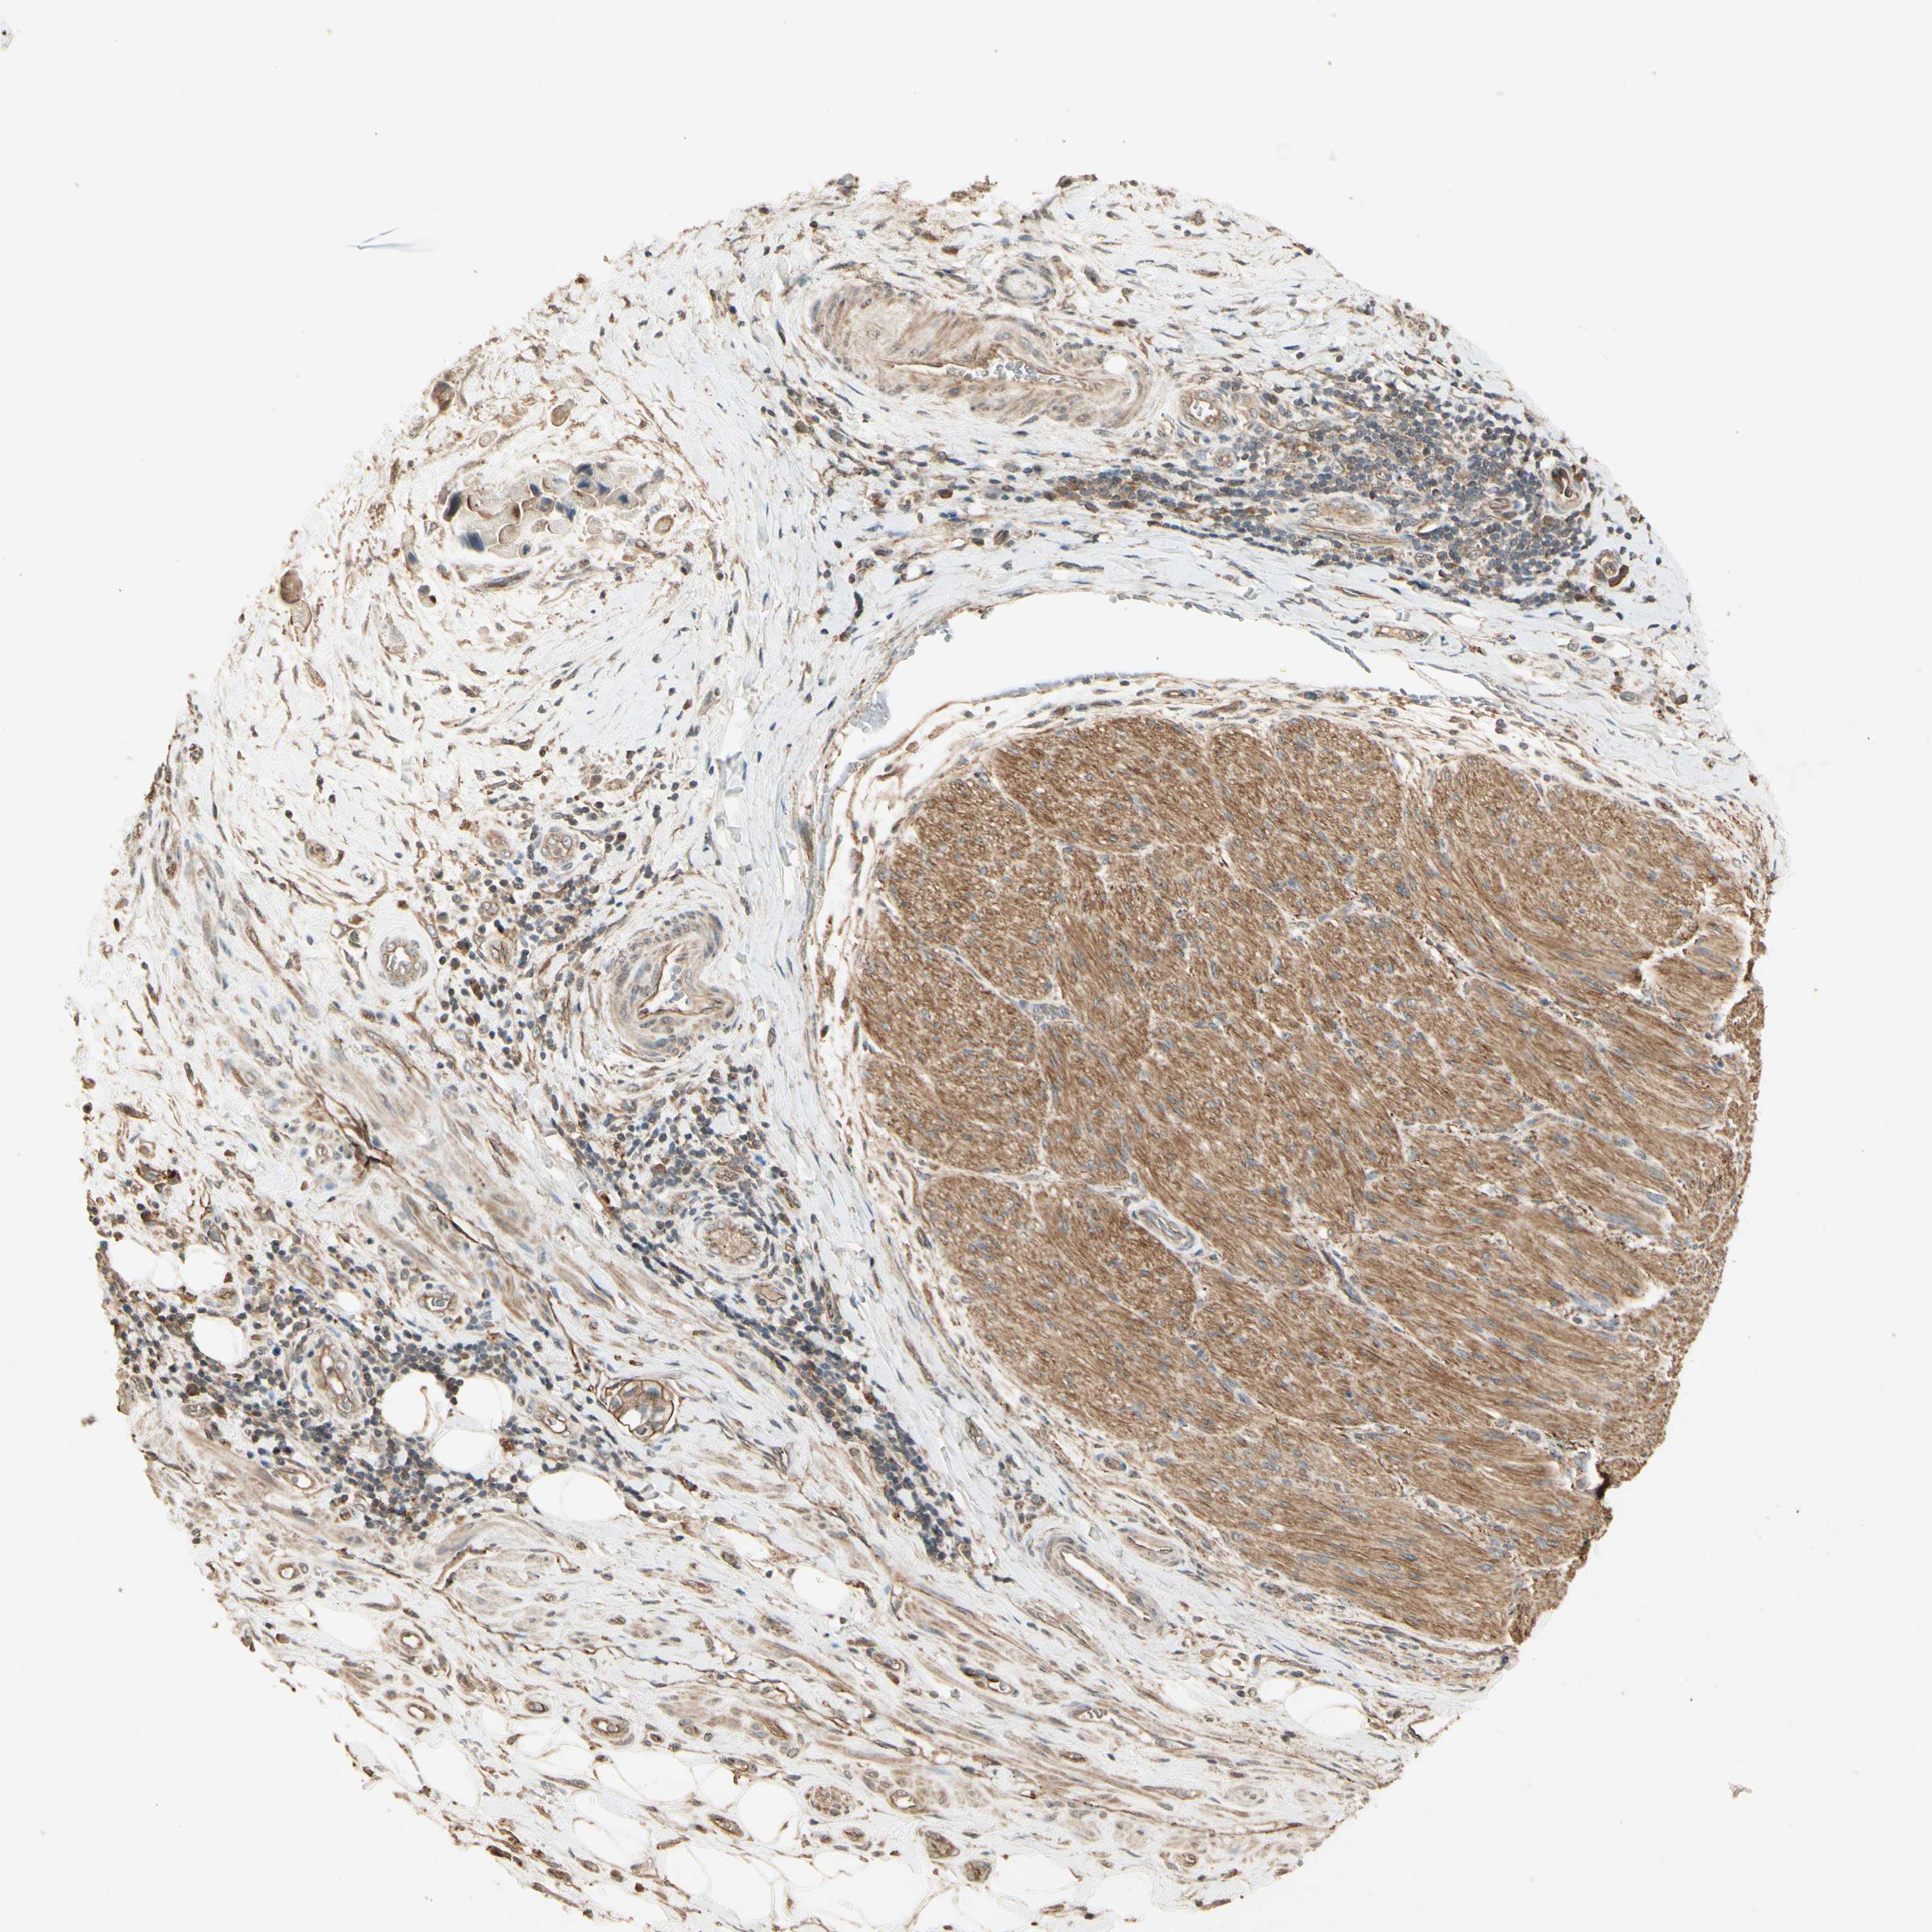

LIVER CANCER - Protein expressioni

A mouse-over function shows sample information and annotation data. Click on an image to view it in a full screen mode. Samples can be filtered based on level of antibody staining by selecting one or several of the following categories: high, medium, low and not detected. The assay and annotation is described here.

Note that samples used for immunohistochemistry by the Human Protein Atlas do not correspond to samples in the TCGA dataset.

Antibody stainingi

Antibody staining in the annotated cell types in the current human tissue is reported as not detected, low, medium, or high, based on conventional immunohistochemistry profiling in selected tissues. This score is based on the combination of the staining intensity and fraction of stained cells.

Each image is clickable and will lead to virtual microscopy that enables deeper exploration of all samples and also displays staining intensity scores, fraction scores and subcellular localization as well as patient and tissue information for each sample.

Antibody HPA006897

Staining

High

Medium

Low

Not detected

Intensity

Strong

Moderate

Weak

Negative

Quantity

>75%

75%-25%

<25%

None

Location

Nuclear

Cytoplasmic/membranous

Cytoplasmic/membranous,nuclear

Cholangiocarcinoma

Carcinoma, Hepatocellular, NOS